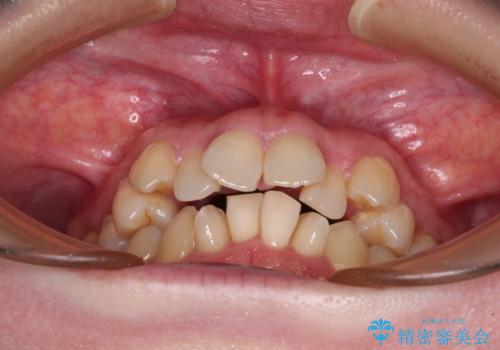

- 上下前歯のデコボコと、上顎の八重歯を気にして来院された患者様です。

下顎に対して上顎が前方にあり、第一大臼歯による咬合状態は上顎前突であったため、上顎のみ左右の第一小臼歯を抜歯し、ワイヤー装置にて矯正治療を行うこととしました。

舌の突出癖が強く、治療途中で上下前歯が乖離した開咬となってしまいました。